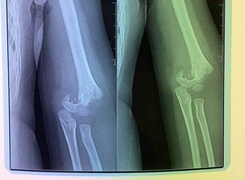

Bệnh viện Đa khoa Hùng Vương (Phú Thọ) vừa tiếp nhận và cấp cứu cho nam thanh niên 28 tuổi nhập viện trong tình trạng đau nhiều, biến dạng, mất vận động khuỷu tay phải.